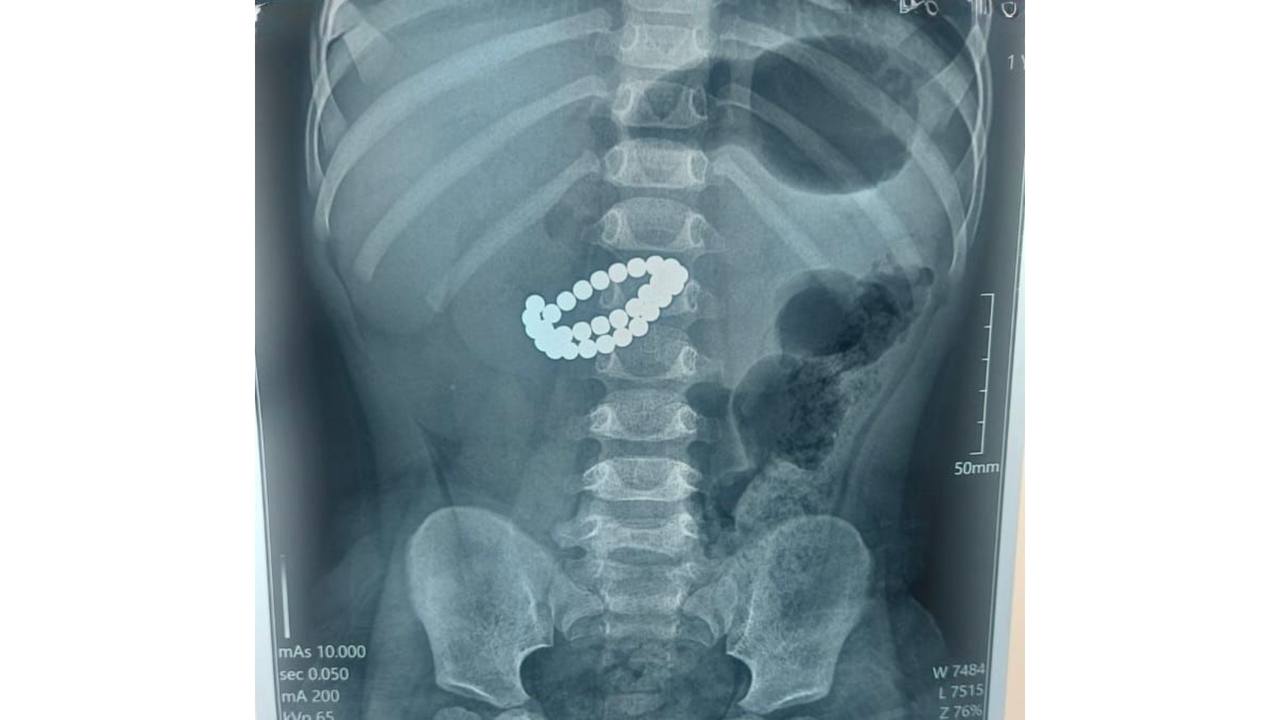

В Алматы хирурги Центра детской неотложной медицинской помощи провели экстренную операцию ребёнку, который проглотил 31 магнит, сообщили в акимате мегаполиса.

Малыш в возрасте 1,9 лет поступил в приёмное отделение в критическом состоянии. Обследование показало, что внутри кишечника находился 31 магнит. Врачи диагностировали множественные перфорации тонкой кишки (отверстия в стенке кишечника) и диффузный каловый перитонит (острое воспаление брюшины).

"Опасность магнитов заключается в том, что, попадая в организм по отдельности, они притягиваются друг к другу уже внутри кишечника. Между ними зажимаются стенки кишки, нарушается кровообращение, начинается некроз (отмирание. – Авт.) тканей, формируются отверстия, и буквально за считаные часы развивается перитонит", – объяснил хирург центра Аскар Ризванов.

Медики выполнили лапаротомию (разрез передней брюшной стенки), извлекли магниты, ушили отверстия в кишке и провели санацию (промывание) брюшной полости.

Врачи подчеркнули, что даже один проглоченный магнит является поводом для немедленного обращения за помощью.